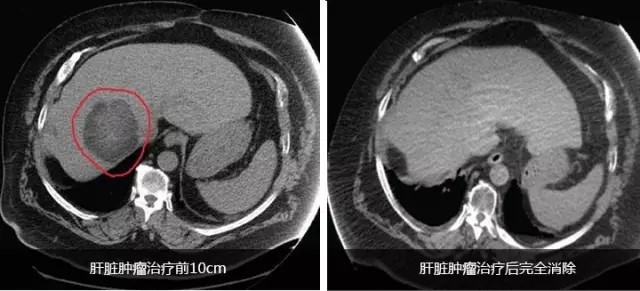

成功案例

患者男性,65岁。2014年10月,患者感到腹部不适、头疼。

检查和诊断结果为

(1)高分化肝细胞癌,大小约10cm,肝硬化明显。

(2)脑转移瘤,左枕叶处有大小约3cm的肿块。

(3)II型糖尿病,需要胰岛素治疗。

(4)慢性肾病;

(5)中度高血压,有心衰病史。

患者处于肝癌晚期,肝癌病灶巨大且有脑转移,国内医疗机构不能实施外科手术治疗。经全球肿瘤医生网请国际癌症专家组远程会诊,患者定于2014年11月10日出国进行EDGE速锋刀无创手术治疗。

半年后,患者身体状态良好,体重明显增加。影像检查报告显示肝脏的巨大肿瘤被彻底清除,脑部肿瘤几乎完全消除,且没有复发。生化检查结果表明肝功能未见异常。